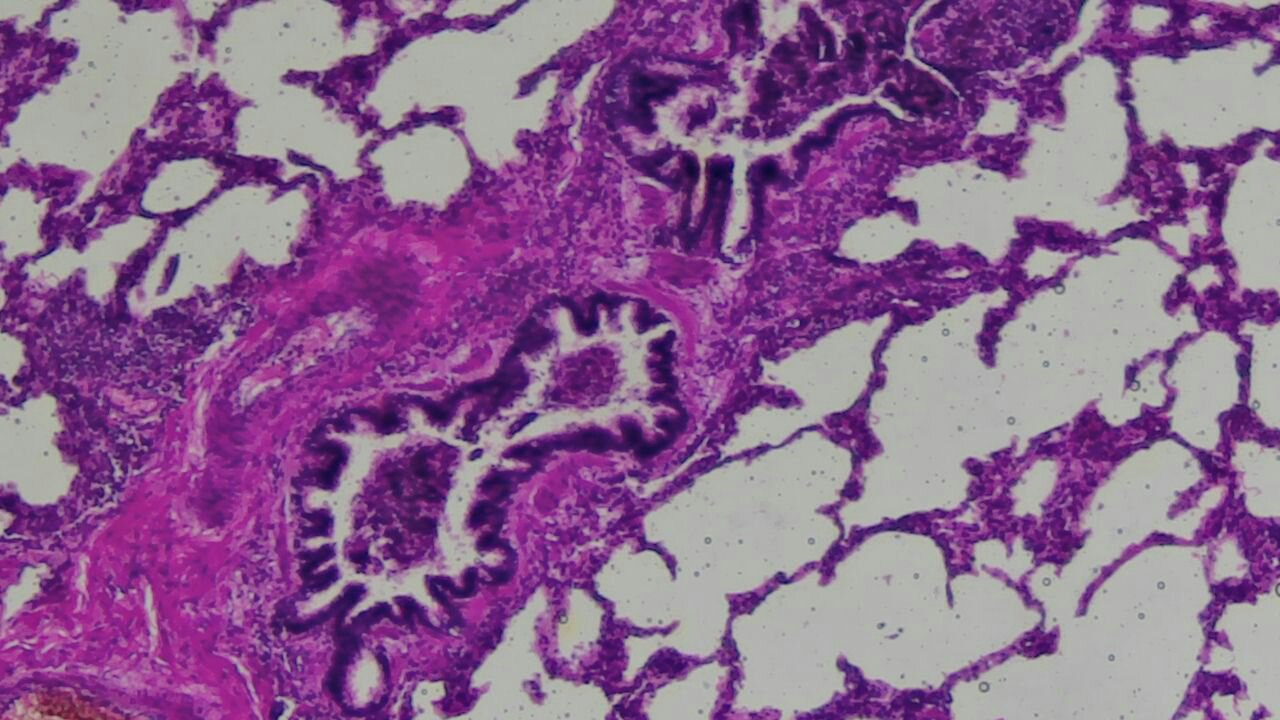

In a number of liver tissue cells, vacuolization of the cytoplasm is observed, in some areas progressing to hydropic dystrophy. The nuclei of hepatocytes are heterogeneous, with detectable karyopyknosis and focal karyolysis, indicating initial necrobiotic changes.Kidneys: Characteristic findings included pronounced dystrophic changes and necrosis of the epithelium of the convoluted tubules, accompanied by interstitial edema and vascular congestion. This corresponds to the morphological picture of acute toxic nephropathy and acute renal failure. The basement membranes of the tubules are generally preserved. The interstitial tissue is moderately edematous, and the microcirculatory vessels are sharply congested, occasionally showing signs of stasis. The lumina of the tubules are unevenly dilated and, in some places, filled with proteinaceous masses, which is consistent with the pattern of acute tubular necrosis. | Figure 3. Glomeruli are generally preserved in configuration; however, some exhibit congestion of the capillary loops, and in certain areas, their moderate collapse. The lumina of the tubules are unevenly dilated and partially filled with proteinaceous masses, consistent with the pattern of acute tubular necrosis. Stained with H&E, mag. 10x20 |

Lungs: Signs of acute lung injury were identified: pronounced interstitial and alveolar edema, capillary congestion, and focal alveolar hemorrhages. These findings reflect severe hemodynamic disturbances and respiratory dysfunction. Heart: Dystrophic changes in cardiomyocytes were noted, including vacuolization, loss of transverse striation, and microcirculatory disorders. This evidence points to toxic-hypoxic myocardial damage and its significant role in thanatogenesis during acute intoxications. | Figure 4. Lung tissue with pronounced signs of acute toxic-hypoxic injury and microcirculatory disorders. Alveoli are unevenly dilated, in some areas sharply overdistended, with focal areas of alveolar collapse. Stained with H&E, mag. 10x20 |

The lumina of a significant portion of the alveoli are filled with pale eosinophilic proteinaceous exudate, consistent with pulmonary edema. Individual alveoli show an admixture of erythrocytes, reflecting diapedetic alveolar hemorrhages. The interalveolar septa are thickened due to pronounced edema and are sharply congested with signs of venous stasis. Capillaries are dilated, occasionally showing phenomena of stasis. Focal infiltration of the septa by occasional mononuclear elements is noted, without the formation of an inflammatory infiltrate.General Discussion of Morphological Findings A comprehensive histological study of the internal organs (heart, liver, kidneys, lungs) revealed a unified complex of morphological changes characteristic of acute exogenous poisoning with a toxic-hypoxic mechanism of thanatogenesis.The sum of the identified histological changes in the internal organs indicates systemic toxic damage to the organism resulting from acute exogenous poisoning. The morphological pattern corresponds to a rapid, fulminant course of intoxication, accompanied by severe tissue hypoxia, impaired microcirculation, and metabolic disorders. These changes have direct thanatogenetic significance and could lead to death due to the combined development of acute cardiovascular and respiratory failure against a background of systemic toxic effects.